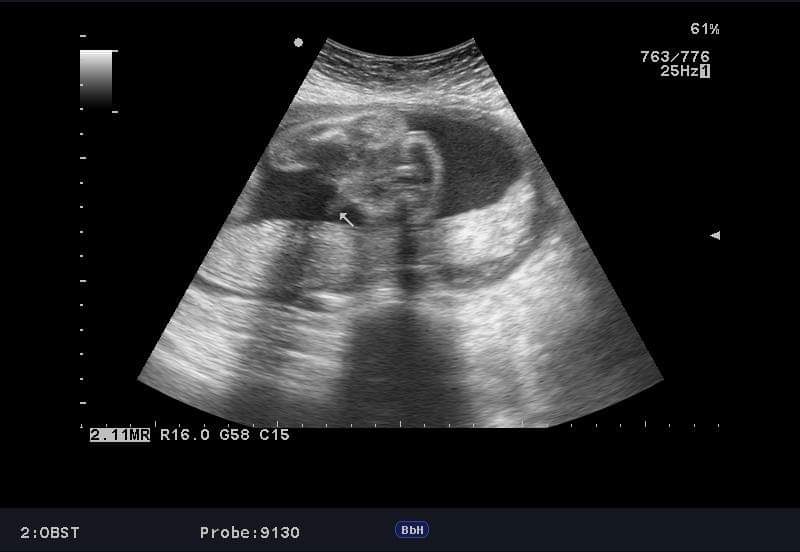

Ahoj holky tak co vidíte? Jsem 27tt a pořád se nám to střídá :(.. Dostali jsme tuto fotecku kde dr. rikal ze to muze byt pupecnik.

My dostali takovou fotecku s tim, ze to bude kluk (fotka z 21.tydne) .... Ve 33. nebo 34. tydnu (ted nevim) jiste na dr rekl, ze to kluk bude (tak snad, do porodu to jiste neni) ..... Ale pro uklidneni, kamaradce 3x rekli, ze to bude kluk a maji Anicku 🙂 jeste se to dozvedet muzes 🙂